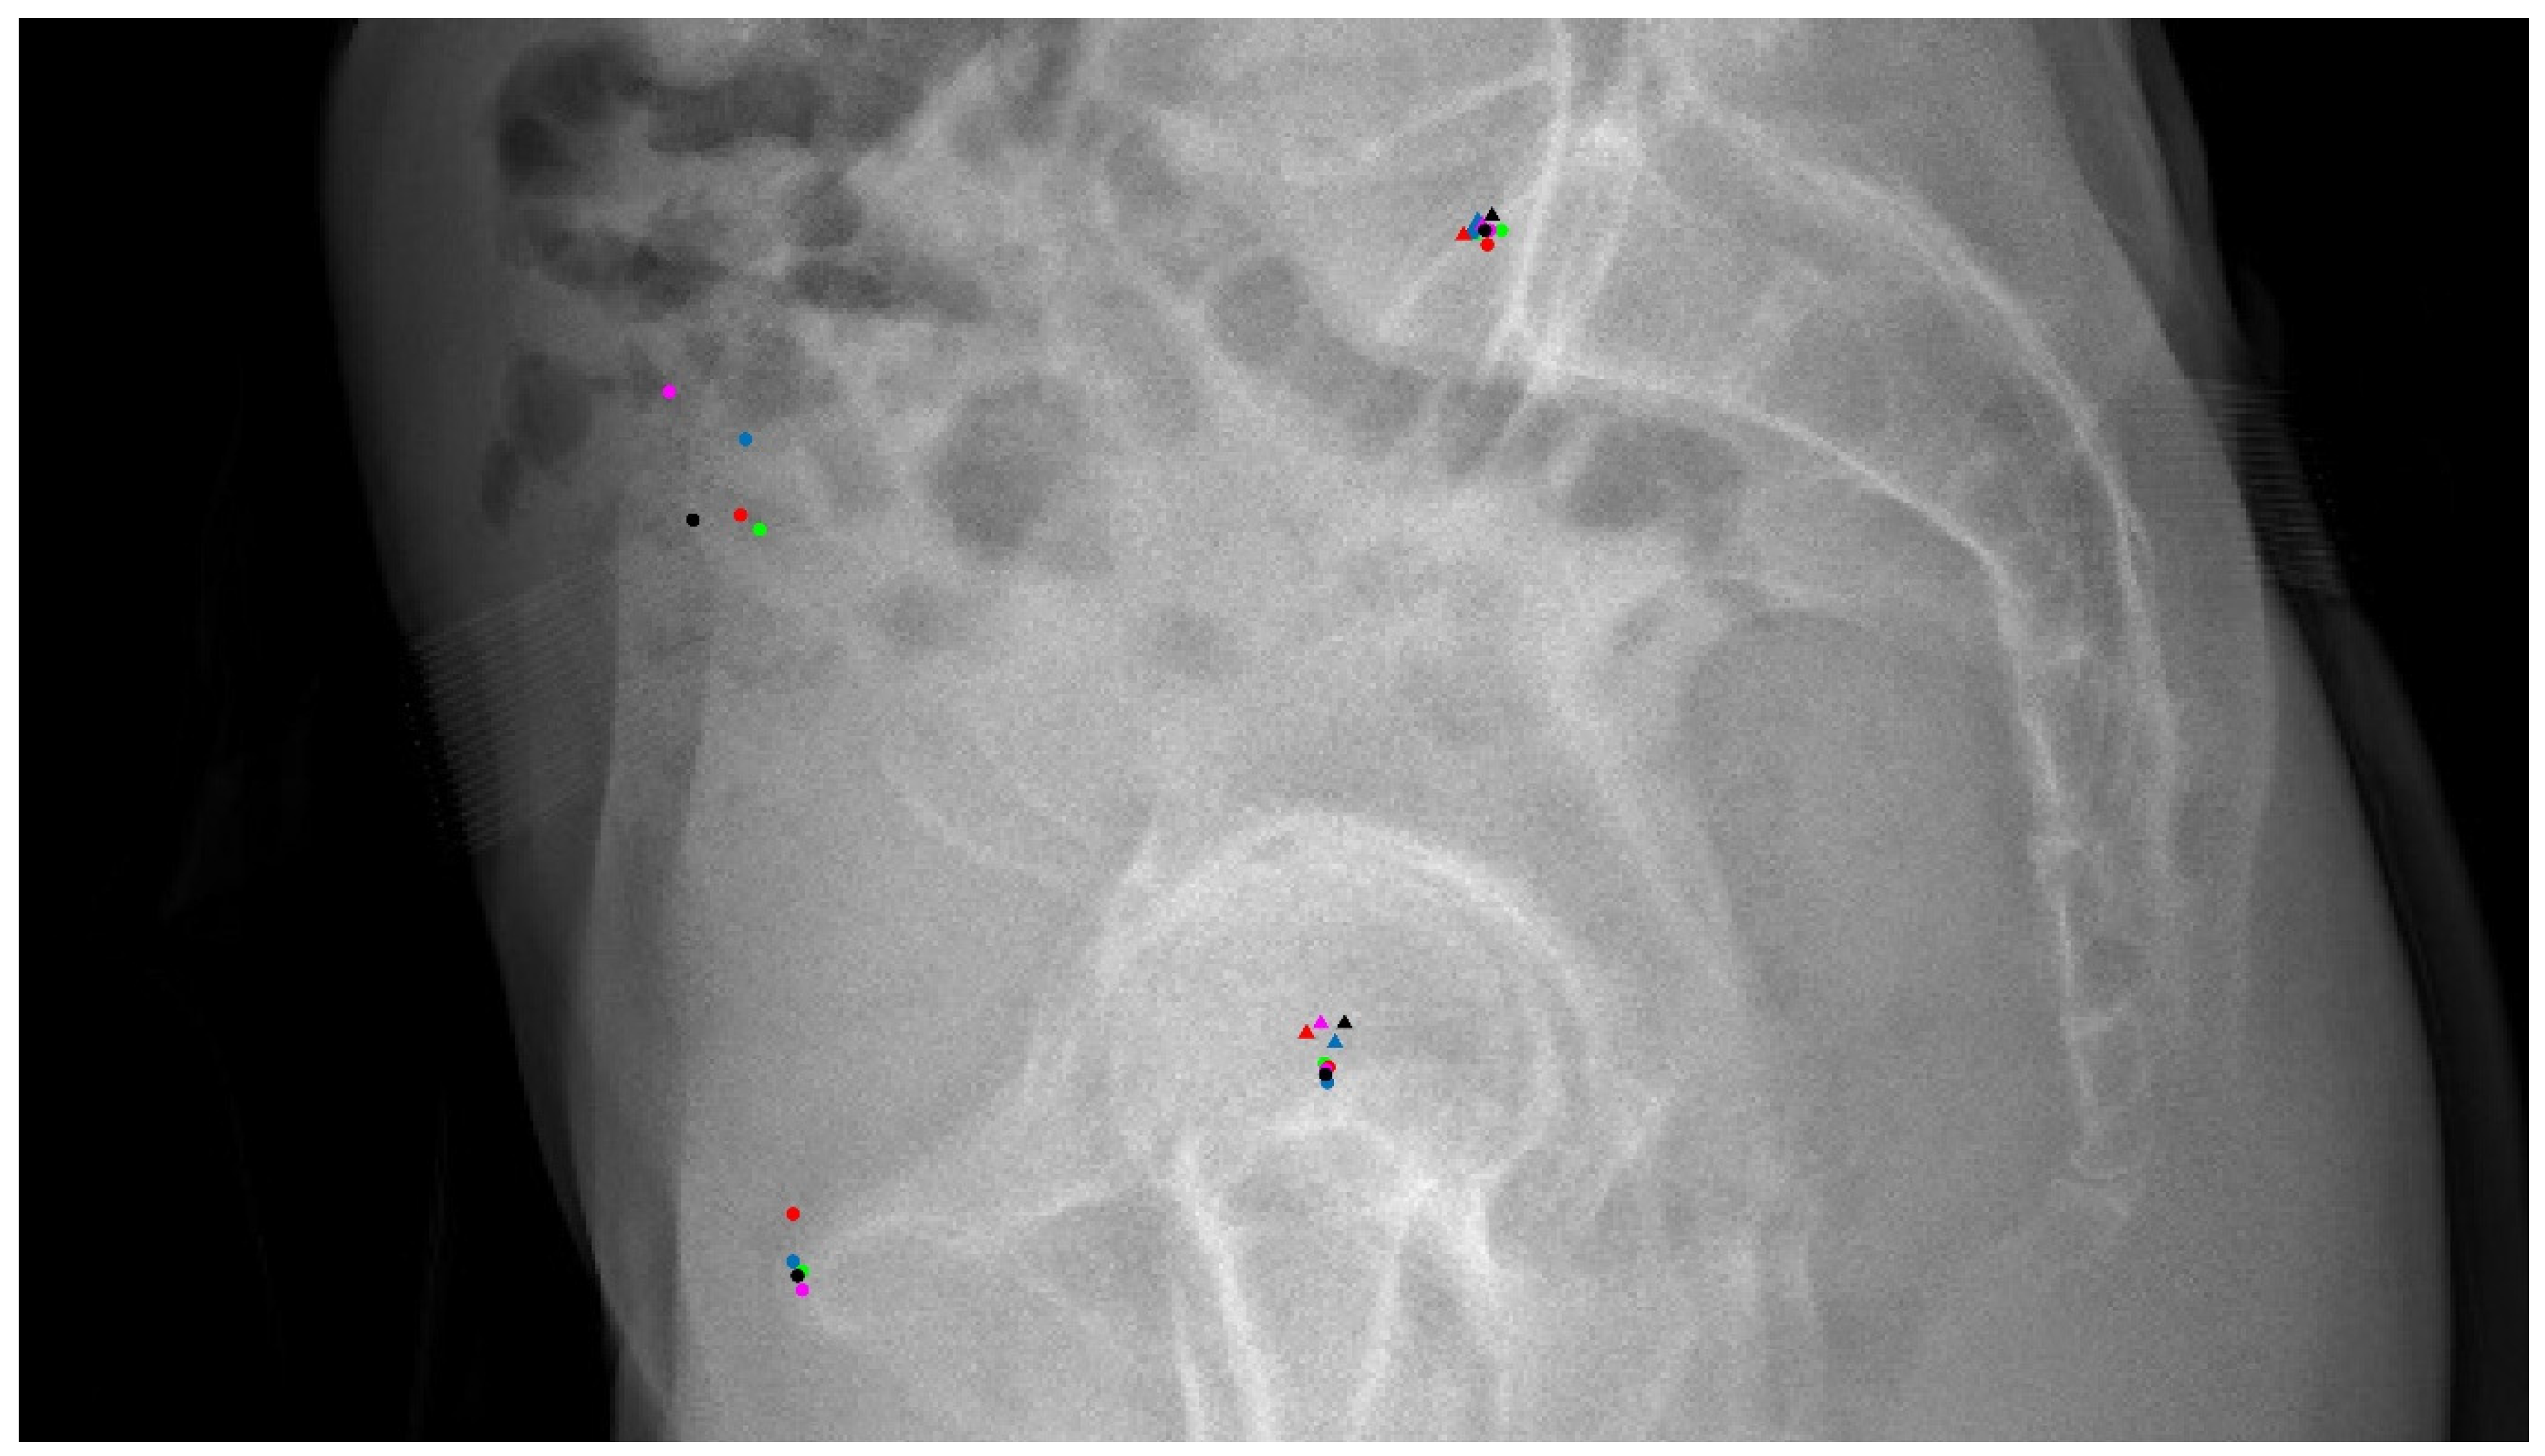

2.2. Landmark Annotations